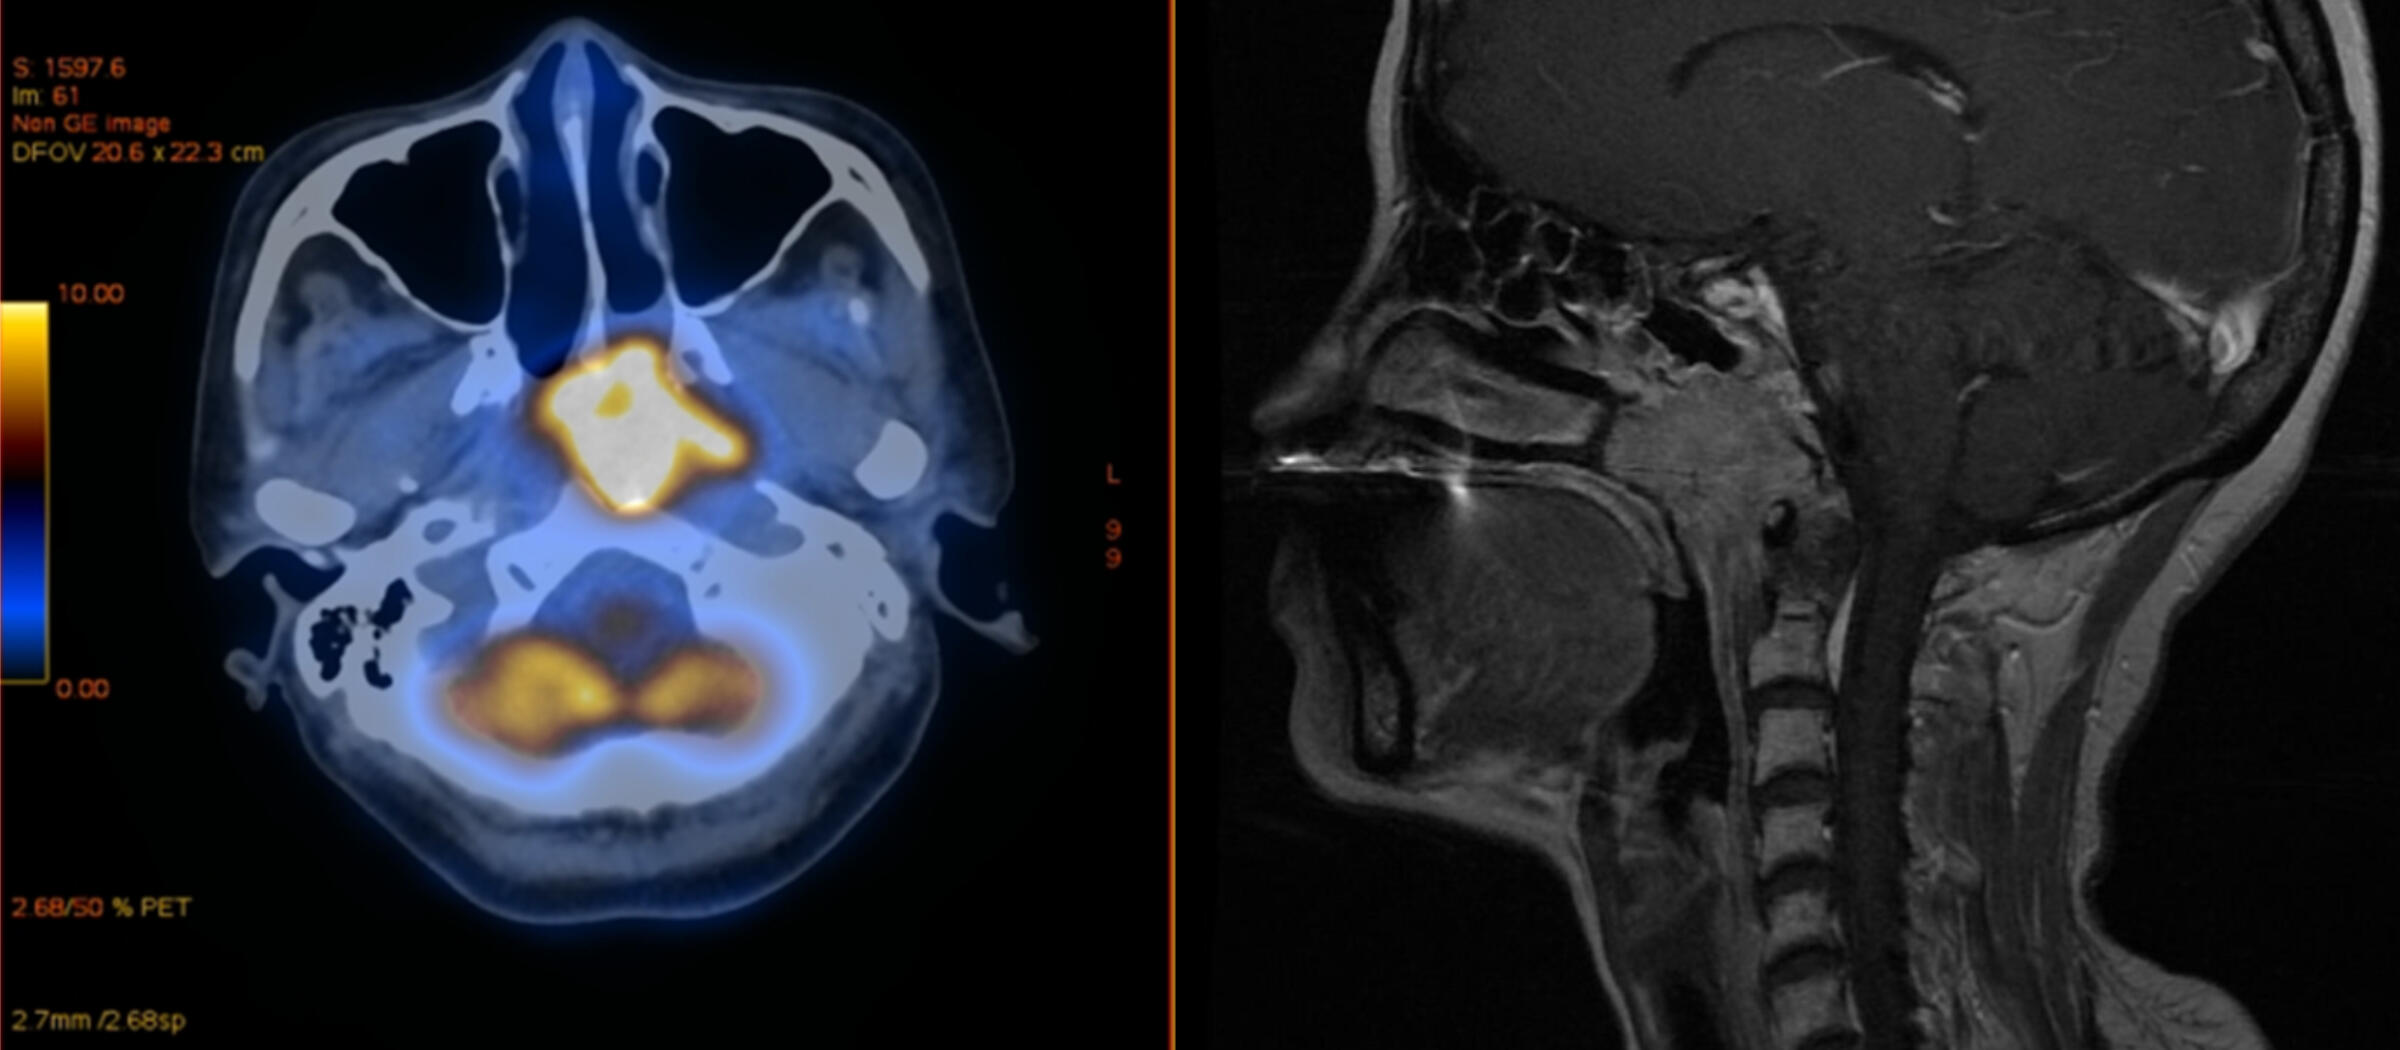

Clinical trial reveals better response to nasopharyngeal cancer treatment with anti-PD1 blockade and chemotherapy in COVID-vaccinated patients

Therapeutic use of checkpoint inhibitors, targeting anti-programmed cell death protein 1 (PD-1), is common in the treatment of nasopharyngeal cancer. Until now, it was feared that vaccination against SarsCoV-2 could reduce the success of anti-PD-1 treatment or cause severe side effects. A recent study by scientists of ImmunoSensation2 at the University of Bonn, together with colleagues at the University of Shanxi in the People's Republic of China now gives the all-clear in this regard. According to the study, the cancer drugs actually worked better after vaccination with the Chinese vaccine SinoVac than in unvaccinated patients. The results are published as a "Letter to the editor" in the journal Annals of Oncology, but are already available online.

A subset of 373 affected individuals had been vaccinated with the Chinese Covid vaccine SinoVac. "Surprisingly, they responded significantly better to anti-PD-1 therapy than the unvaccinated patients," explains Prof. Dr. Christian Kurts, Director of the IMMEI at the University Clinics Bonn and member of the Transdisciplinary Research Area "Life & Health". "Furthermore, they did not experience severe side effects more often."